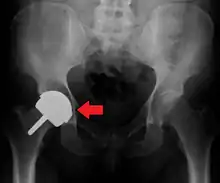

Hemiarthroplasty

Hemiarthroplasty is a surgical procedure that replaces one half of the joint with an artificial surface and leaves the other part unchanged. This class of procedure is most commonly performed on the hip after an intracapsular fracture of the femur neck (hip fracture). The procedure is performed by removing the head of the femur and replacing it with a metal or composite prosthesis. The most commonly used prosthesis designs are the Austin Moore and Thompson prostheses. A composite of metal and HDPE that forms two interphases (bipolar prosthesis) can be used. The monopolar prosthesis has not been shown to offer any advantage over bipolar designs. The procedure is recommended only for elderly/frail patients, due to their lower life expectancy and activity level. This is because over time the prosthesis tends to loosen or to erode the acetabulum.[86] Independently mobile older adults with hip fractures may benefit from a total hip replacement instead of hemiarthroplasty.[87]

Hip prosthesis for hemiarthroplasty. This example is bipolar, meaning that the head has two separate articulations.

X-ray of the hips, with a right-sided hemiarthroplasty